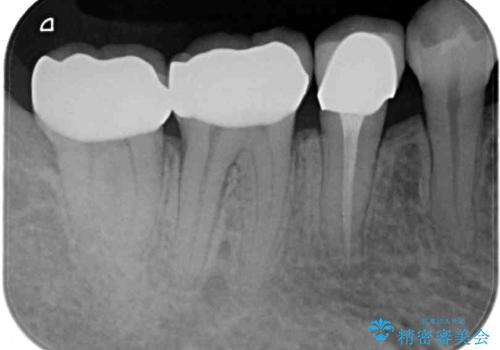

ドイツやベルギーなどで治療を受けた奥歯2本が食事の度にしみているとのことで、レントゲン検査や視診を行ったところ、補綴物や修復物の適合が悪く、それが原因であると考えられました。

いずれの歯も症状に異常なく、オールセラミッククラウンにて補綴治療を行うこととしました。

歯とクラウンの適合が良くなることで、食事の度にしみるという症状はなくなり、歯間部にものが挟まって不快な思いをすることもなくなりました。